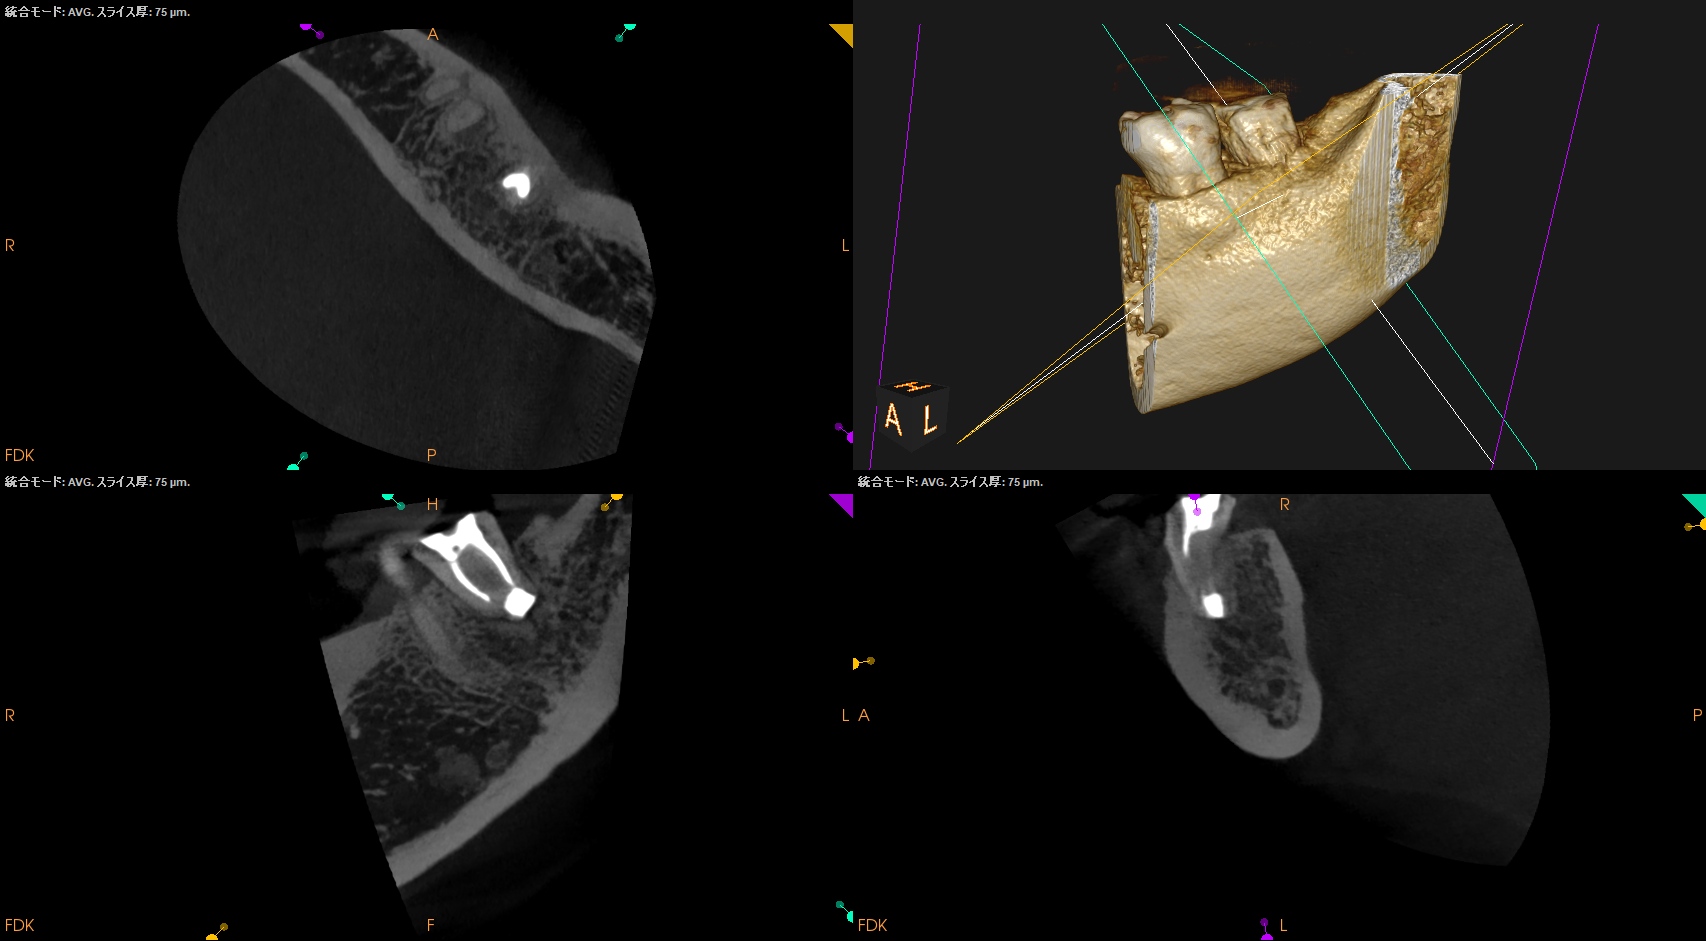

#18 Intentional Replantation 1.5yr recall(2025.11.25)

5年前から悩まされていた歯肉の腫脹は消失し、歯槽骨も完治した。

打診検査時のアンキローシス音もないことからこの日で終診とさせていただいた。